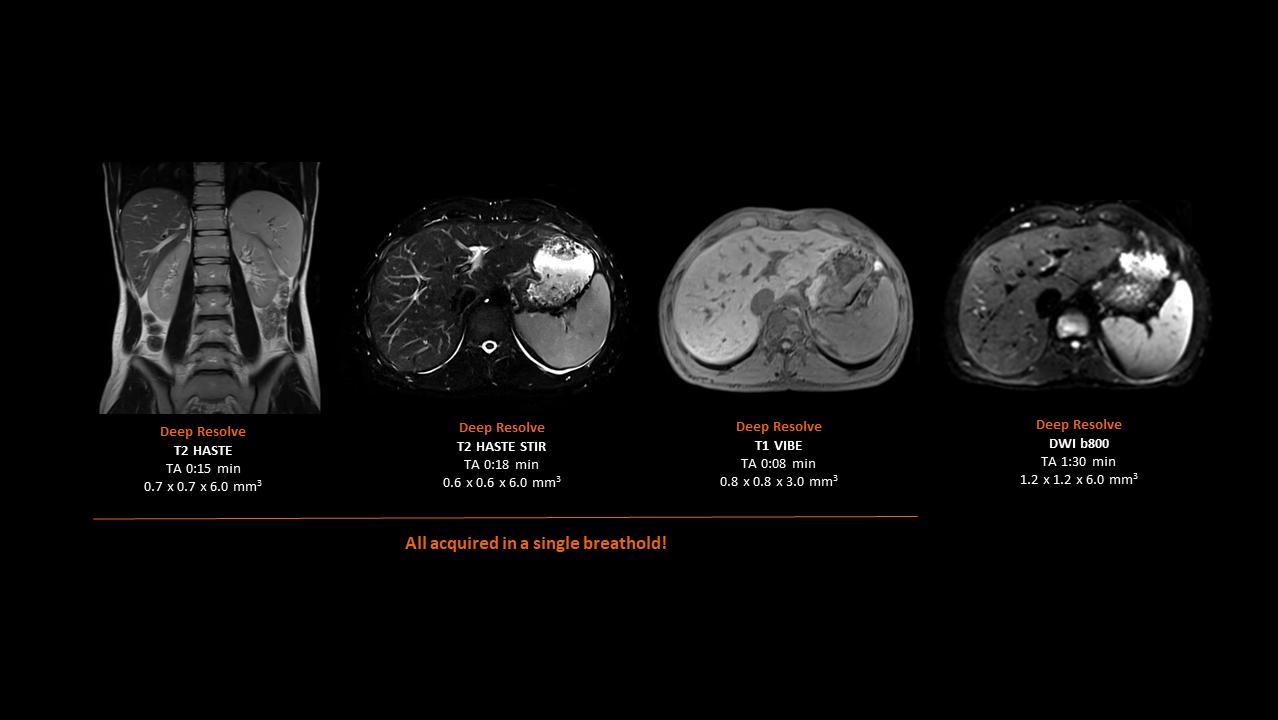

Deep Resolve will be at the forefront of the revolution in MRI acceleration. Deep Resolve will enable our fastest MRI, with images that will have extraordinary clarity, higher clinical productivity, and an even better patient experience. This transformational effect of Deep Resolve is now planned to expand to 3D5, unlocking a new dimension in MRI image resolution and speed.

More about Deep Resolve